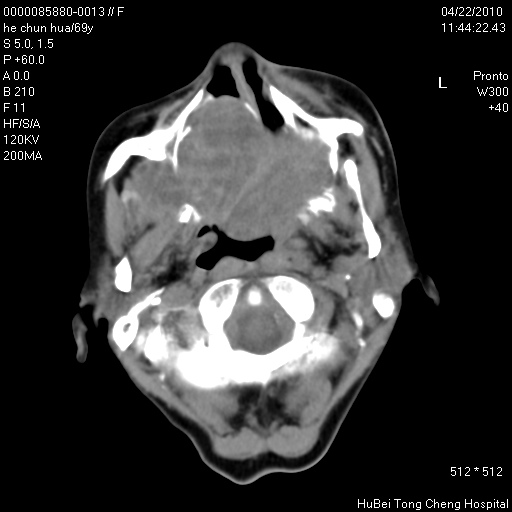

标题: CT25937:女,69Y

硬腭部包块十余年,渐进性增大。